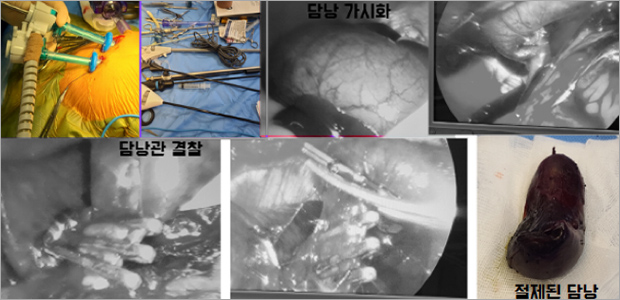

복강경 수술 케이스

복강경 담낭절제술

케이스1

- 수술 1주차

- 수술 2주차

케이스2

- 수술 4일차

- 수술 3주차

초음파로 몇 년간 관찰해오다가 담낭이 파열되기 전에 수술로 제거하기로 결정하고

예은동물의료센터를 찾아오게 되었습니다. 개복수술과 복강경 수술 두가지 방법으로 진행할 수 있었고

딥 체스트 독이기 때문에 개복을 하게되면 복강경 수술보다 절개부위가 커져 더 아플 수도 있고

회복 속도도 길 수 있다고 해서 복강경으로 진행하게 되었습니다.

수술 전 수액 처치할 때 같이 있게 해주셔서 좋았고, 수술 후에도 회복 속도가 빨라서 금방 퇴원할 수 있게

되었습니다. 통원 치료하면서 집에 돌아갔을 때 갑자기 구토를 한다던가 했을 때 연락드리면 바로바로

답장해주셔서 더 마음이 놓였던 것 같습니다. 입원했을 때 잘 돌봐주시고, 검사 결과도 알기 쉽게

설명해주셔서 좋았습니다. 수술 무사히 잘 해주셔서 감사합니다.